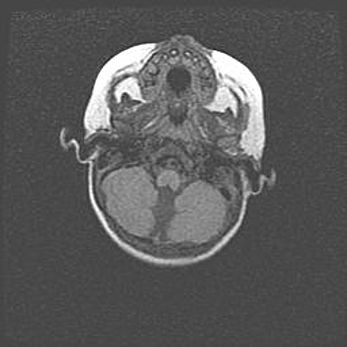

Мальформация Денди-Уокера. Киста задней черепной ямки.

Агенезия мозолистого тела.

Возраст: 2,5 месяца

Вес: 2420 г

Пол: женский

Окружность головы: 37 см

Срок гестации: 32 недели

Мальформация Денди—Уокера — редкий вид патологии ЦНС, представляющий собой врожденный порок развития каудального отдела ствола и червя мозжечка, ведущий к неполному раскрытию срединной (Мажанди) и латеральных (Лушка) апертур IV желудочка мозга. Для этогно синдрома характерна триада симптомов: гипотрофия червя мозжечка и/или полушарий мозжечка, кисты задней черепной ямки, гидроцефалия различной степени. В 70% случаев порок сочетается и с другими аномалиями головного мозга, в частности с агенезией мозолистого тела.